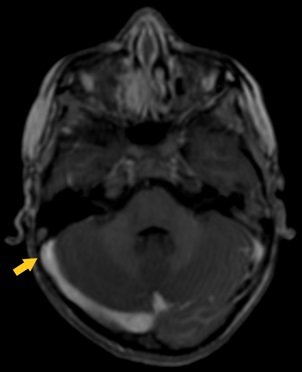

Al alta se realizó control con RM cerebral donde ambos senos transversos fueron permeables. En la imagen axial T1 EG 3D (eco de gradiente) (Fig. 2) se observa desaparición del trombo alojado en el seno transverso derecho.